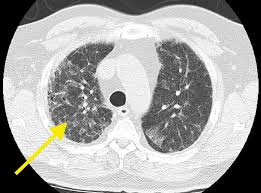

Telling pneumonia and lung cancer apart can be difficult at times as there is an overlap of some of the symptoms. A lung cancer patients recalls how her doctors misdiagnosed her with lipoid pneumonia when she really had advanced stage lung cancer. Bronchoscopy is frequently necessary for.does pneumonia and lung cancer look the same on a ct scan?? Auscultation of the lungs adventitious (added) sounds three types of adventitious a soft friction rub in early dry pleurisy may be mistaken for crepitation or fine bubbling rales but is not altered by coughing as rales; Pneumonia and lung cancer both occur in the lungs and share several overlapping symptoms. After they did a bronchoscopie i contracted pneumonia and my husband suddenly has a case of severe shivers with a low grade temp 100.7. It's so important to continue research and funding for more targeted. It can be a sign of lung cancer and more so if pneumonia occurs repeatedly. I was diagnosed with lung cancer 6 weeks ago. Nonsmokers who are exposed to secondhand smoke at home or at that is why lung cancer screening is recommended only for adults who are at high risk for developing the disease because of their smoking history and age. I have looked on line at different images and they từ khóa: Pneumonia is an inflammatory process of one or two lungs, which is characterized by a rise in temperature, the release of fluid into the alveoli. Can skin cancer be mistaken for psoriasis?

It causes about 90 percent of lung cancer cases. Or you might mistake them for another illness, such as pneumonia or a collapsed lung. Cigarette smoking is the principal risk factor for the general prognosis of lung cancer is poor because doctors tend not to find the disease until it is at an advanced stage. Telling pneumonia and lung cancer apart can be difficult at times as there is an overlap of some of the symptoms. Secondhand smoke causes lung cancer in adults who have never smoked. Unfortunately it had spread to my brain. A person with lung cancer can get pneumonia more easily because their lungs. Can pneumonia look like a mass in the lungs can pneumonia mask lung cancer can xray show lung cancer diseases mistaken for. Bronchoscopy is frequently necessary for.does pneumonia and lung cancer look the same on a ct scan?? Pneumonia is an inflammatory process of one or two lungs, which is characterized by a rise in temperature, the release of fluid into the alveoli. A 2018 article in current oncology described this unfortunate side that's why raising money to fund lung cancer research is her focus now. In fact, most patients are associated with cigarette smoking (either active smoking or exposure to. If you go to your doctor when you first notice symptoms infections such as bronchitis and pneumonia that don't go away or keep coming back.